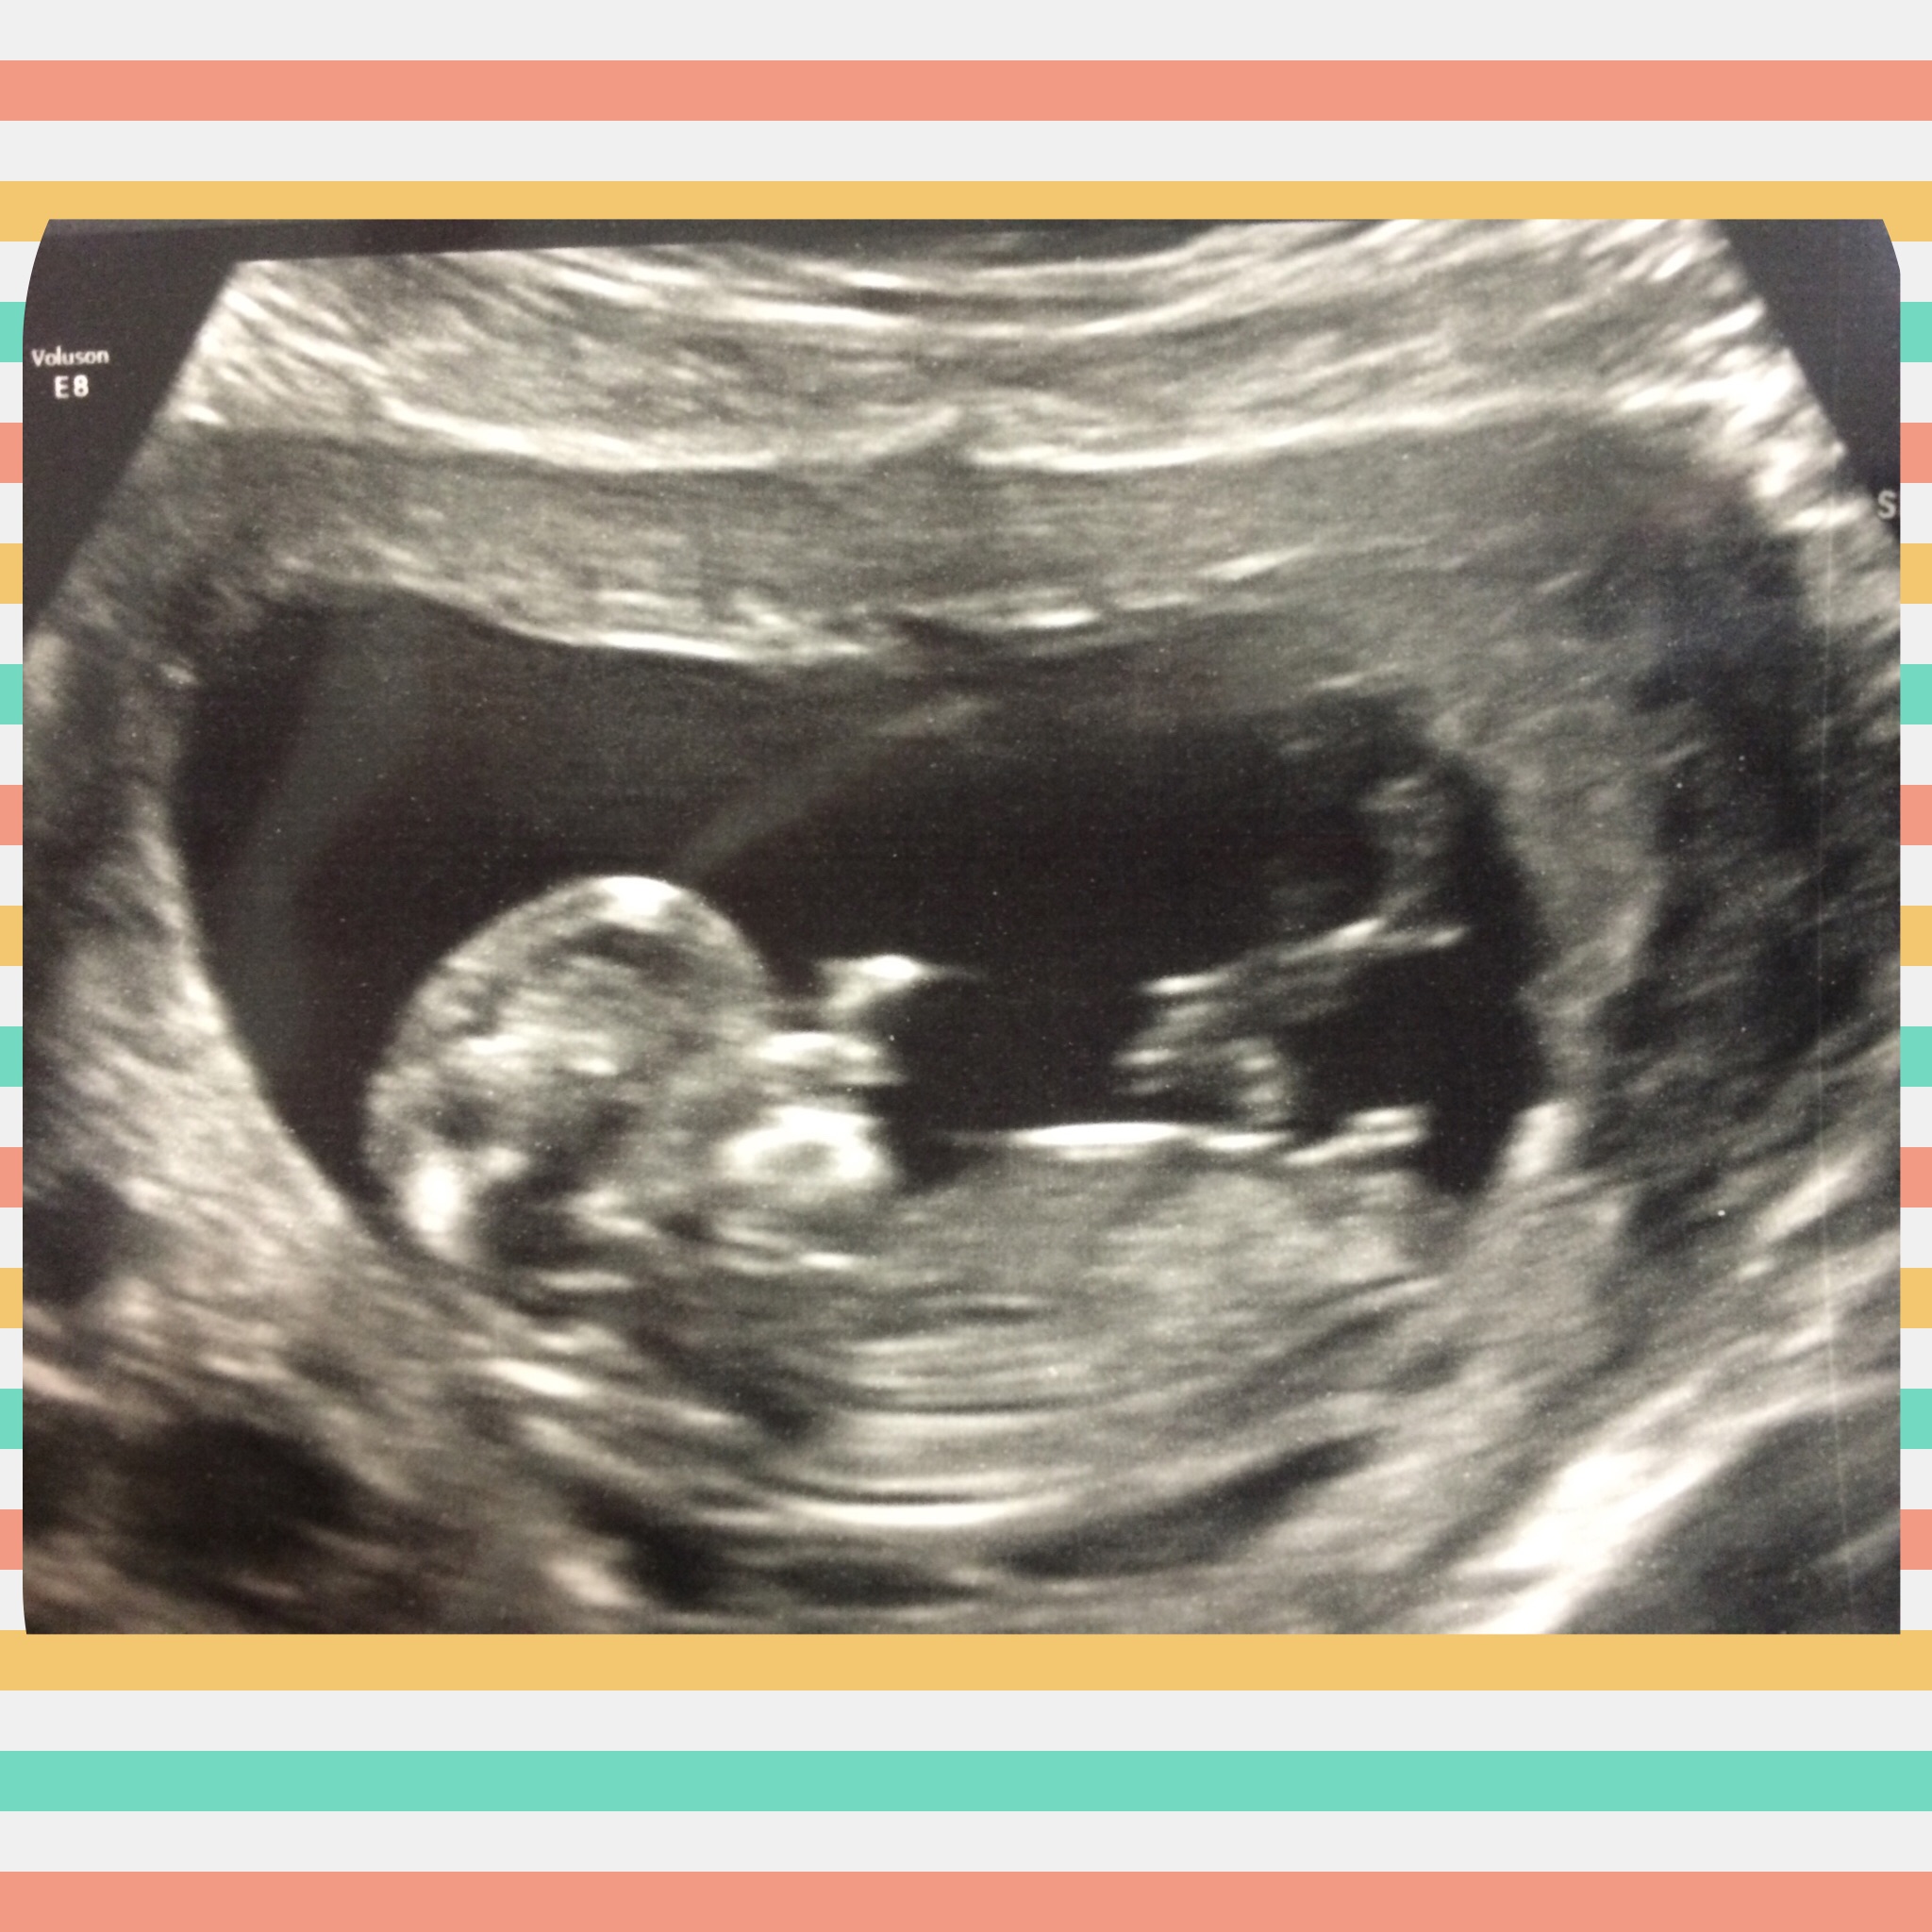

Here is my most recent ultrasound pic. It was great to get an abdominal scan this time and their gel was warm! Our little pumpkin was moving all over the place with a heart rate of 164! I brought my mom and she got a great kick out of seeing it all! This was 11w6d.

We also graduated up one whole day! 12w 1d today.